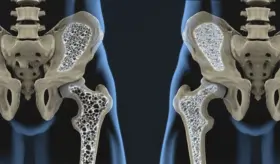

#InfografíaMSP La artrosis desgasta el cartílago que recubre las articulaciones, afectando su movilidad y provocando dolor, rigidez e inflamación. A medida que avanza, puede alterar por completo la estructura de zonas como rodillas, caderas, columna y manos.

Existen múltiples opciones terapéuticas según la etapa de la artrosis, desde tratamientos conservadores (fisioterapia, analgésicos, ortesis) hasta intervenciones quirúrgicas avanzadas, como prótesis articulares y técnicas mínimamente invasivas.